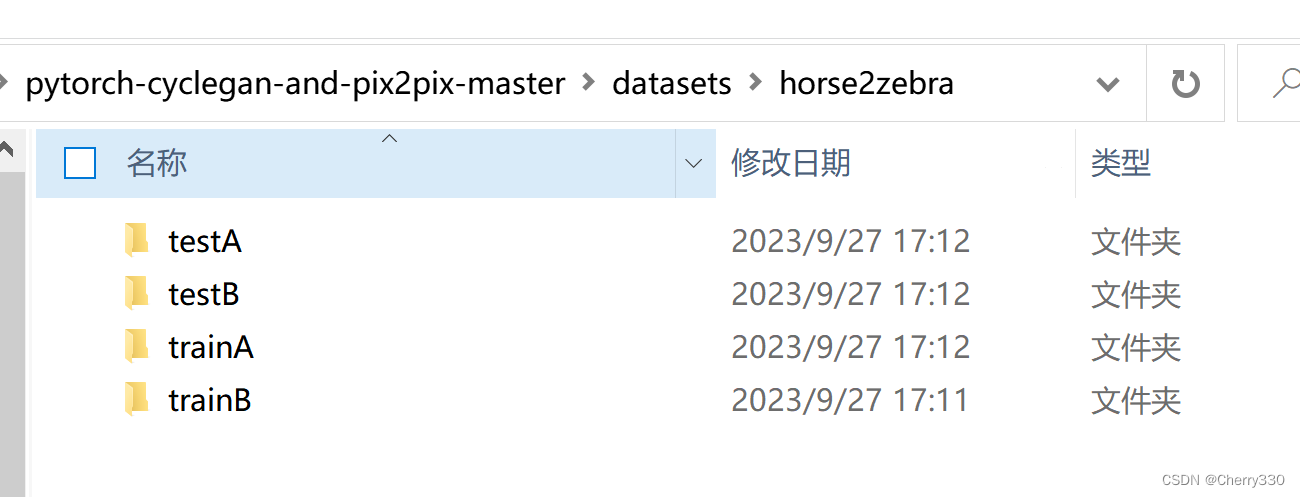

第二步,数据准备。我这边是做的核磁共振T2转T1。大家在datasets文件夹中创建一个horse2zebra文件夹(如图3)。

图3 horse2zebra文件夹

horse2zebra文件夹构成如下(图4)。大家将对应的图片放入文件夹中。数据集就完成啦~

图4 horse2zebra文件夹构成